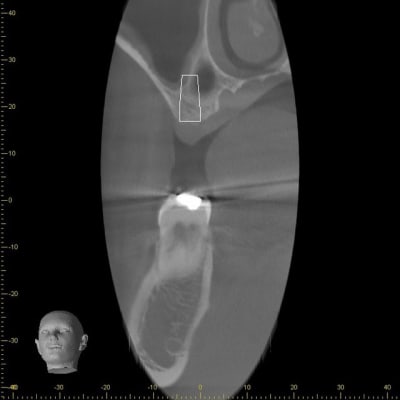

Voilà le résultat à 5 mois:

J'ai opté pour une implantation au niveau de 16 dans le septa avec un "pseudo summers latéral" et d'un sinus lift au niveau de 17.

J'ai commencé par la 16 en prévenant le patient qu'en cas de perforation de la membrane au niveau de 16, nous reporterions la pose de 17 à plus tard.

Pour la 16 je me suis suis servi du kit d’expansion de MIS, qui m'a permit de positionner mon implant sans perforer la membrane de schneider.

Puis 17 : sinus lift classique.

Poley controle sinus cakvjl - Eugenol